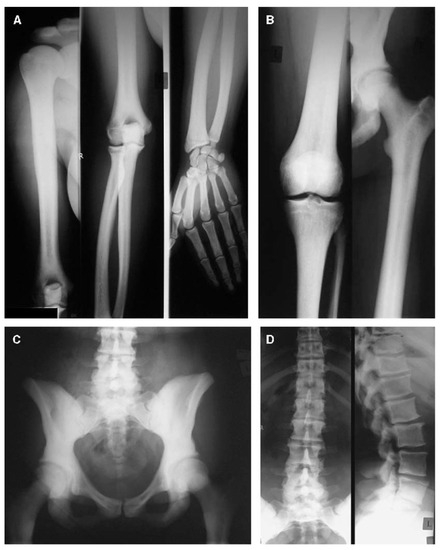

- Zhao, D.; Sun, L.; Zheng, W.; Hu, J.; Zhou, B.; Wang, O.; Jiang, Y.; Xia, W.; Xing, X.; Li, M. Novel mutation in LRP5 gene cause rare osteosclerosis: Cases studies and literature review. Mol. Genet. Genomics. 2023, 298, 683–692. [Google Scholar] [CrossRef]